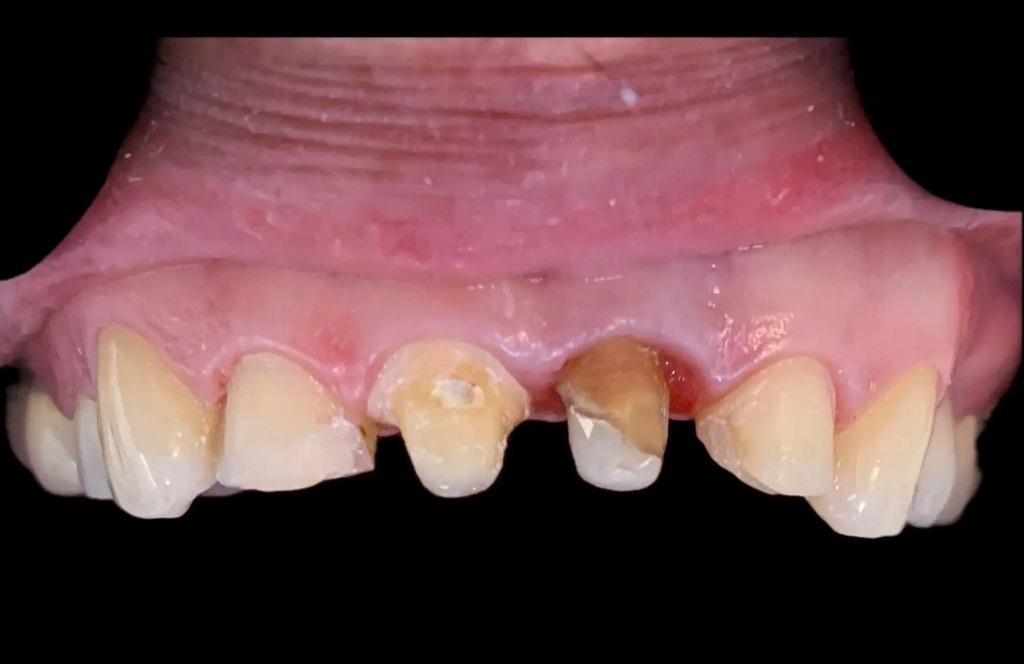

Подготовка к установке временной коронки была проведена через восемь недель после хирургической экструзии. На этом приеме наблюдалось активное костное ремоделирование, главным образом в периапикальной области (фото 3). Этот процесс ремоделирования характеризуется потерей костной массы в области гребня в первые шесть-восемь недель после операции. Окончательная реставрация была проведена через три месяца после первоначальной процедуры, чтобы обеспечить достаточное время для заживления тканей пародонта и тем самым предотвратить рецессию десен после реставрации. Непосредственно перед установкой окончательной реставрации наблюдались здоровые ткани пародонта, хорошая симметрия десневого края и соответствующая длина обода (фото 4).

Фото 4: Клиническая ситуация непосредственно перед установкой окончательной реставрации.